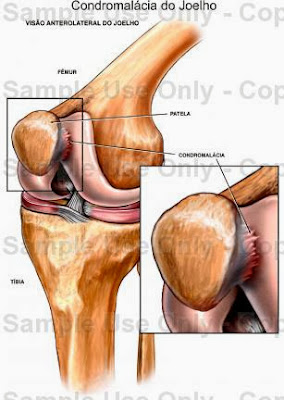

Mulheres são mais susceptíveis a ter condromalácia patelar

Por ser a maior e mais complexa articulação do corpo humano e por suportar quase todo o peso do corpo, é muito comum que o joelho sofra lesões ao longo da vida. Entre elas está a Condromalácia Patelar, doença que causa degeneração da superfície da cartilagem, localizada na parte da patela. Mais comum entre as mulheres, a patologia é causada por uma instabilidade ou formato da rótula e o desvio de eixo dos membros inferiores, joelhos muito afastados ou muito juntos.